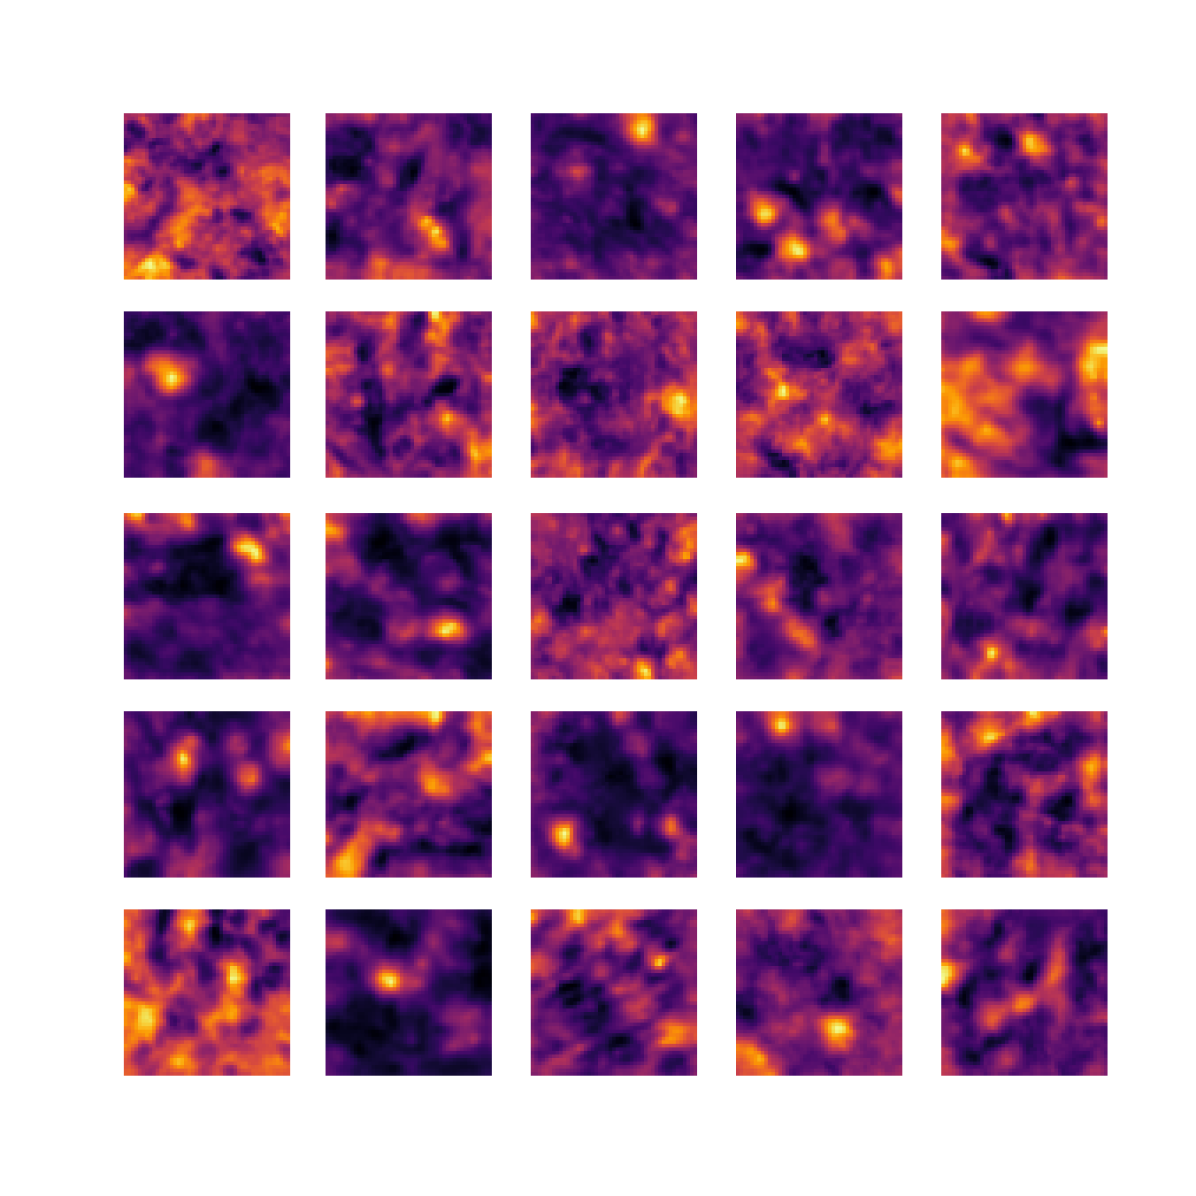

We also analyse the activation maps for each model using GradCAM as described in section S3. This offers more insight into the areas of the image which are contributing most heavily to the models’ representations. In Figure 4(b) we present some representative examples, however, a larger selection which was chosen at random is presented in Figures S10 to S25. The larger selection makes it easier to see the emergent patterns, including that privileged Siamese models tend to mainly identify features which are strongly present in both inputs, while unprivileged Siamese models tend to learn more diffuse features that are not specific to one cell phenotype or image region. TriDeNT ♆ incorporates both sets of features, learning both features specific to the privileged data and more the general features associated with unprivileged Siamese networks.

We can see in Figure 4(b) panel A that for ERG, the privileged Siamese model focuses almost exclusively on any nuclei which could be endothelial cells. As there are very few endothelial cells in the dataset, it could be an effective strategy to identify anything that could potentially be an endothelial cell to minimise the difference between the representations of the H&E model and the IF mask model. In the corresponding unprivileged Siamese image, we see that the model identifies some of these nuclei, albeit less strongly, but also focuses heavily on the other tissue and even the background, while strongly fixating on two spots of debris in the center of the image. This model has less ‘incentive’ to learn the weak features related to endothelial cells as these occur rarely and are not easy to detect, while more generic strong features such as the presence of connective tissue and the prevalence of background are more common and predictable from augmented images. We see that TriDeNT ♆ combines these two feature sets, strongly identifying nuclei while also identifying the connective tissue.

In panel C we see a similar pattern, with the privileged Siamese model fixating solely on the nuclei, while the TriDeNT ♆ model takes a more balanced approach. The unprivileged Siamese model appears to focus on a single cluster of nuclei while neglecting others, and similarly identifies an area of fibroblasts with its distinctive pattern but does not others.

In contrast to panels A and C which represent models with poor privileged Siamese results, panels B and D represent models whose privileged Siamese results were comparable to both TriDeNT ♆ and even the supervised baseline. It is therefore interesting to note that there are far more similarities between the privileged Siamese and TriDeNT ♆ models in both cases. Particularly in panel B, TriDeNT ♆ and the privileged Siamese model return virtually identical heatmaps, with both strongly identifying epithelial nuclei and neglecting the same areas of connective tissue. The unprivileged model in this case appears to focus solely on the centre of the image, giving a significantly different heatmap to the other panels.

Panel D again shows the previous pattern, with the privileged Siamese model identifying the features strongly present in the privileged data – fibroblasts – while neglecting the nuclei present. TriDeNT ♆ also strongly identifies the connective tissue, but, unlike the privileged Siamese model, does not completely neglect the nuclei. The unprivileged Siamese model primarily identifies background, and does not appear to identify the nuclei in this example.